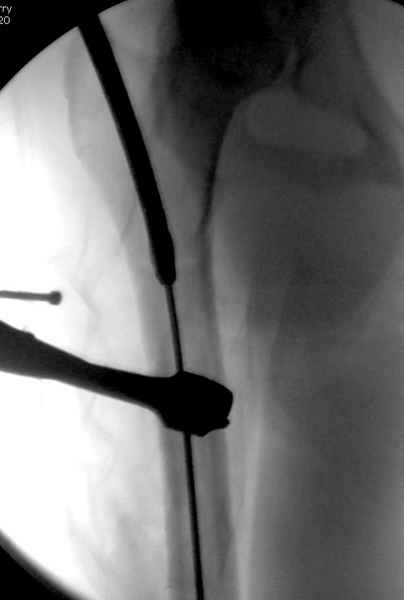

Как раз недавно у меня был примерный случай: больному 36 лет, поступил ночью, травма в результате мотоциклетной аварии, кроме чрезвертельного и спирального перелома левого бедра имеется переломы костей предплечья с этой же стороны. Скелетное вытяжение, а на следующий день больной про оперирован на ортопедическом столе с дистракцией. Чтобы не расколоть чрезвертельный перелом провели временную спицу ближе к переднему кортексу, из малого разреза костодержатель для репозиции, а фиксацию провели антиградным штифтом. Этапы операции на снимках.

Больной долго оставался нестабильным, только на 14 день удалось заменить на антеградный интромедуллярный штифт TFN (trochanteric femoral nail) SmithNephew. После неудачной попытки закрытой репозиции, несмотря на использование "joystick", проксимальный стержень от

наружного фиксатора, (перелом начал срастаться) репозицию провели из малого доступа, затем остальные этапы операции.

Случай был представлен из-за того, что больного оперировали после наружной фиксации и был риск инфекцирования через места проведения стержней (на снимках), прошло больше 3 месяцев, выписан из амбулаторной службы из-за отсутсвия надобности дальнейшего наблюдения.